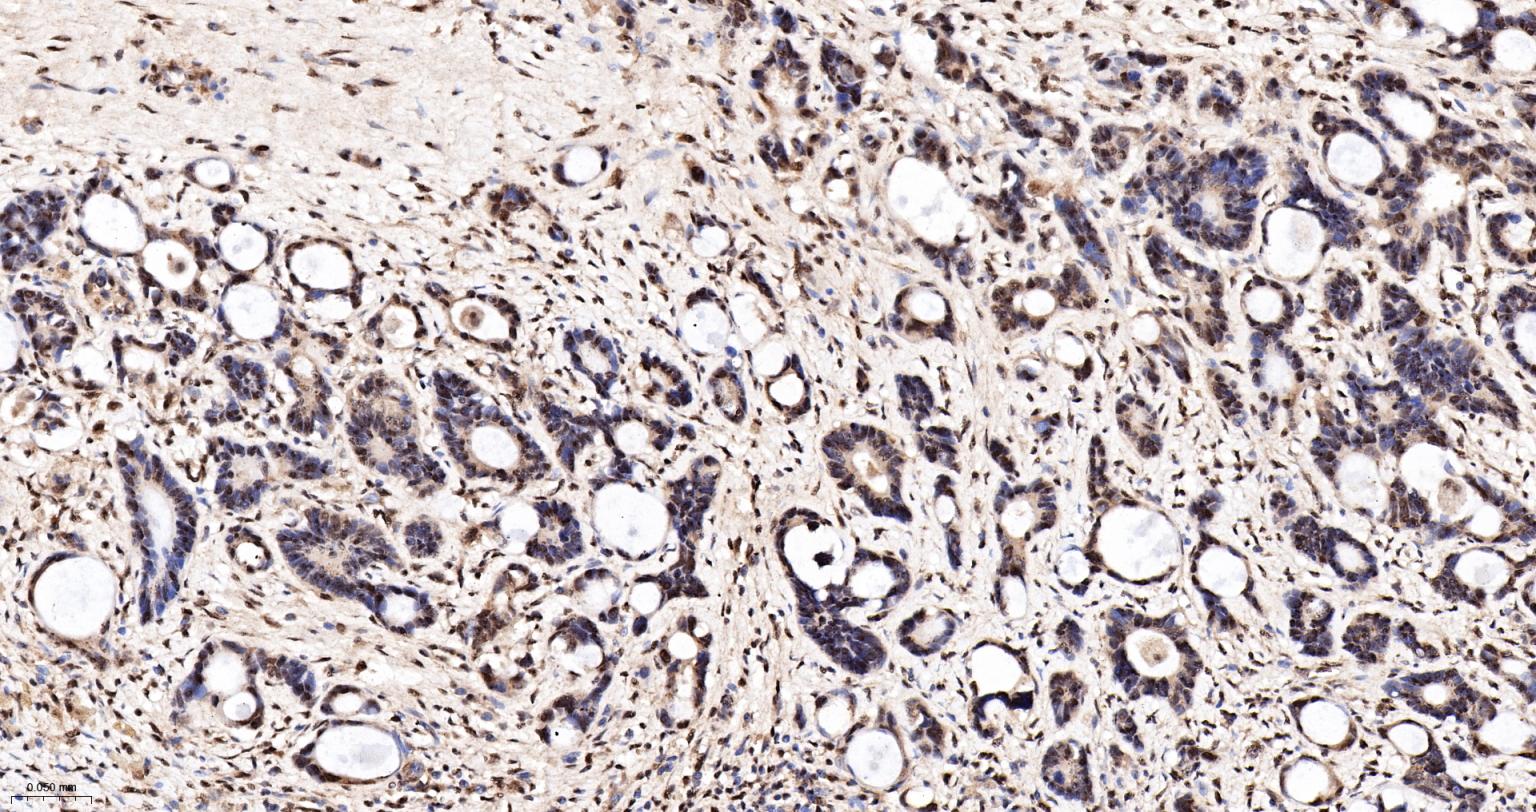

Paraformaldehyde-fixed, paraffin embedded Human Ovarian Cancer; Antigen retrieval by boiling in sodium citrate buffer (pH6.0) for 15 min; The section was incubated with PELP1 Monoclonal Antibody, Unconjugated (bsm-61154R) at 1:200 overnight at 4°C, followed by conjugation to the bs-0295G-HRP and DAB (C-0010) staining.